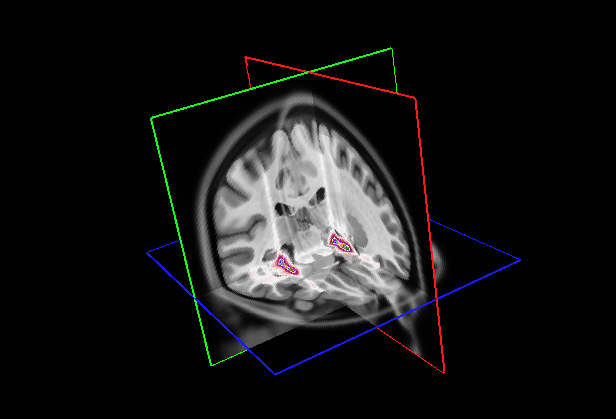

Refer to caption

(a)

(b)

Figure 8: GradCAM++ visualization of five slices for each plane selected randomly for our model (a) and Attention Transformer (b)

Figure 9: (Left) Visualization of mean 3D GradCAM++ map of entire dataset overlapped to MNI152 template with our model; (Right) Visualization of mean 3D GradCAM++ map of entire dataset overlapped to MNI152 template with Attention Transformer;

We also examined the interpretability of the Attention Transformer model proposed in (Altay et al., 2021). For comparison, we created 2D saliency maps using the GradCAM++ algorithm (Chattopadhay et al., 2018) across all three views and all five test sets from the different folds. These maps were combined to create a unified average 3D saliency map as outlined in Section 7. This method was also applied to generate equivalent results from the saliency maps produced using our diagnostic model. As shown in Fig. 8, the 2D maps produced by our method are generally sparser compared to those from the Attention Transformer. The method introduced in (Altay et al., 2021) employs a cross-attention mechanism via a Multi-Head. Therefore, it is plausible that the Multi-Head allows to generate 2D maps that align more meaningfully within the 3D context. This finding suggests that our approach may consider less contextual information from adjacent slices unless it is particularly relevant. In contrast, the cross-attention in the Attention Transformer might enable a more cohesive representation of the entire 3D space by considering both the local features within slices and their contextual interactions. This behavior is further clarified by creating 3D maps and overlaying them on the MNI152 template, similar to the attentional maps. As illustrated in Fig. 9 on the left, the 3D maps created using our model cover a broader and less concentrated area compared to those produced by the Attention Transformer, which are shown on the right. However, similar to the 3D attentional maps, both models predominantly focus on an area surrounding the hippocampus. As detailed in Table 9, both models identify key areas, such as the hippocampus and the amygdala, as significant. However, the emphasis on other regions varies markedly between the two. In the attention transformer model, there is a noticeable focus on the inferior lateral ventricles and the parahippocampal region, areas less emphasized by our model in this case. This result indicates that the Attention Transformer using cross-attention in combination with GradCAM can produce results similar to those obtained by our method with a 3D attentional map. As seen in Tables 8(a) and 9(b), the first four areas on which our model focused with our approach are the same as those focused on by Attention Transformer with GradCAM. In contrast, our model with GradCAM shows broader involvement with regions such as the superior and middle temporal areas, which are not as prominent in the other cases.